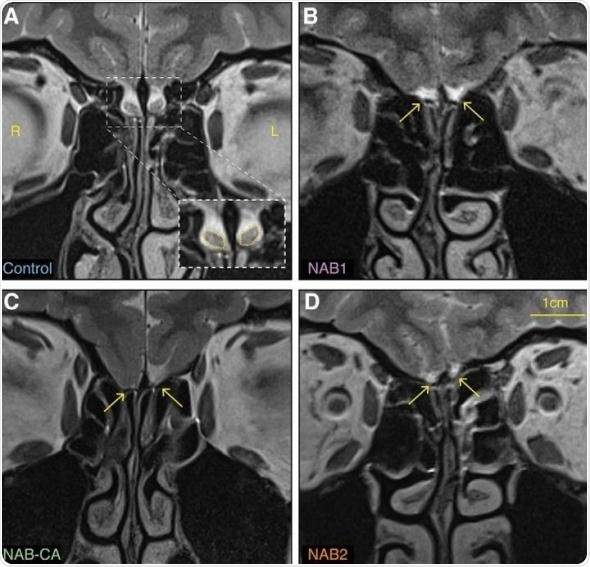

Sobel's team first stumbled upon a person who could smell despite lacking apparent olfactory bulbs while reviewing MRIs of healthy, left-handed female volunteers for a different smell study. Upon reviewing just nine more MRIs of left-handed women, the researchers found another woman missing discernible olfactory bulbs.

In hopes of finding a physical explanation, the researchers ran even more scans of the original two volunteers and of a 33-year-old woman with no identifiable olfactory bulbs and congenital anosmia. After MRIs, diffusion MRIs, ultra-high definition 3D imaging, and whole-brain voxel-based morphometry, they concluded that yes, all three of the women had no visible olfactory bulbs but otherwise normal brain structures outside the olfactory system.